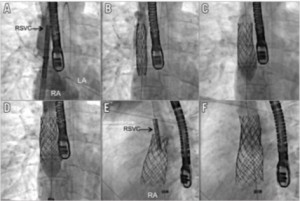

手技は全身麻酔下、経食道超音波サポート下に行います。大腿静脈穿刺でアクセスを作製し、まず心房中隔穿刺、心房中隔アプローチで右肺静脈にプロテクトワイヤーを留置します*。次に大腿静脈から上大静脈まで進めたサイジングバルーンを拡張し、血管サイズの測定と経食道エコーでの残存シャントの有無を確認します。また同時に肺静脈の造影と肺静脈内同時圧測定によりステント留置時に狭窄や閉塞をきたさないかを評価します。治療可能と判断される場合は、カバードステント(covered Cheatham-Platinum stent, NuMED社)を上大静脈から右心房上縁にかけて留置します。またステント固定不良に対してはステントの上部に追加ステントを行い対応しています(図4, 5)。

平均年歴53歳(38-66歳)の5症例に対して治療を施行し、全例で手技に成功し、手技合併症も認めませんでした。また平均8.1ヵ月の観察期間で、全例に運動耐容能の改善が得られています。さらに論文報告の後、現在までに20症例近くの治療が施行され、全例が治療に成功しています。また、手技合併症は心房中隔穿刺の合併症によるタンポナーデ症例1例のみで、同症例もドレナージで改善しており重篤な合併症は認めておりません。全例6ヶ月後にCTで経過フォローを行い、現在までステント脱落や損傷は認めません(図6)。